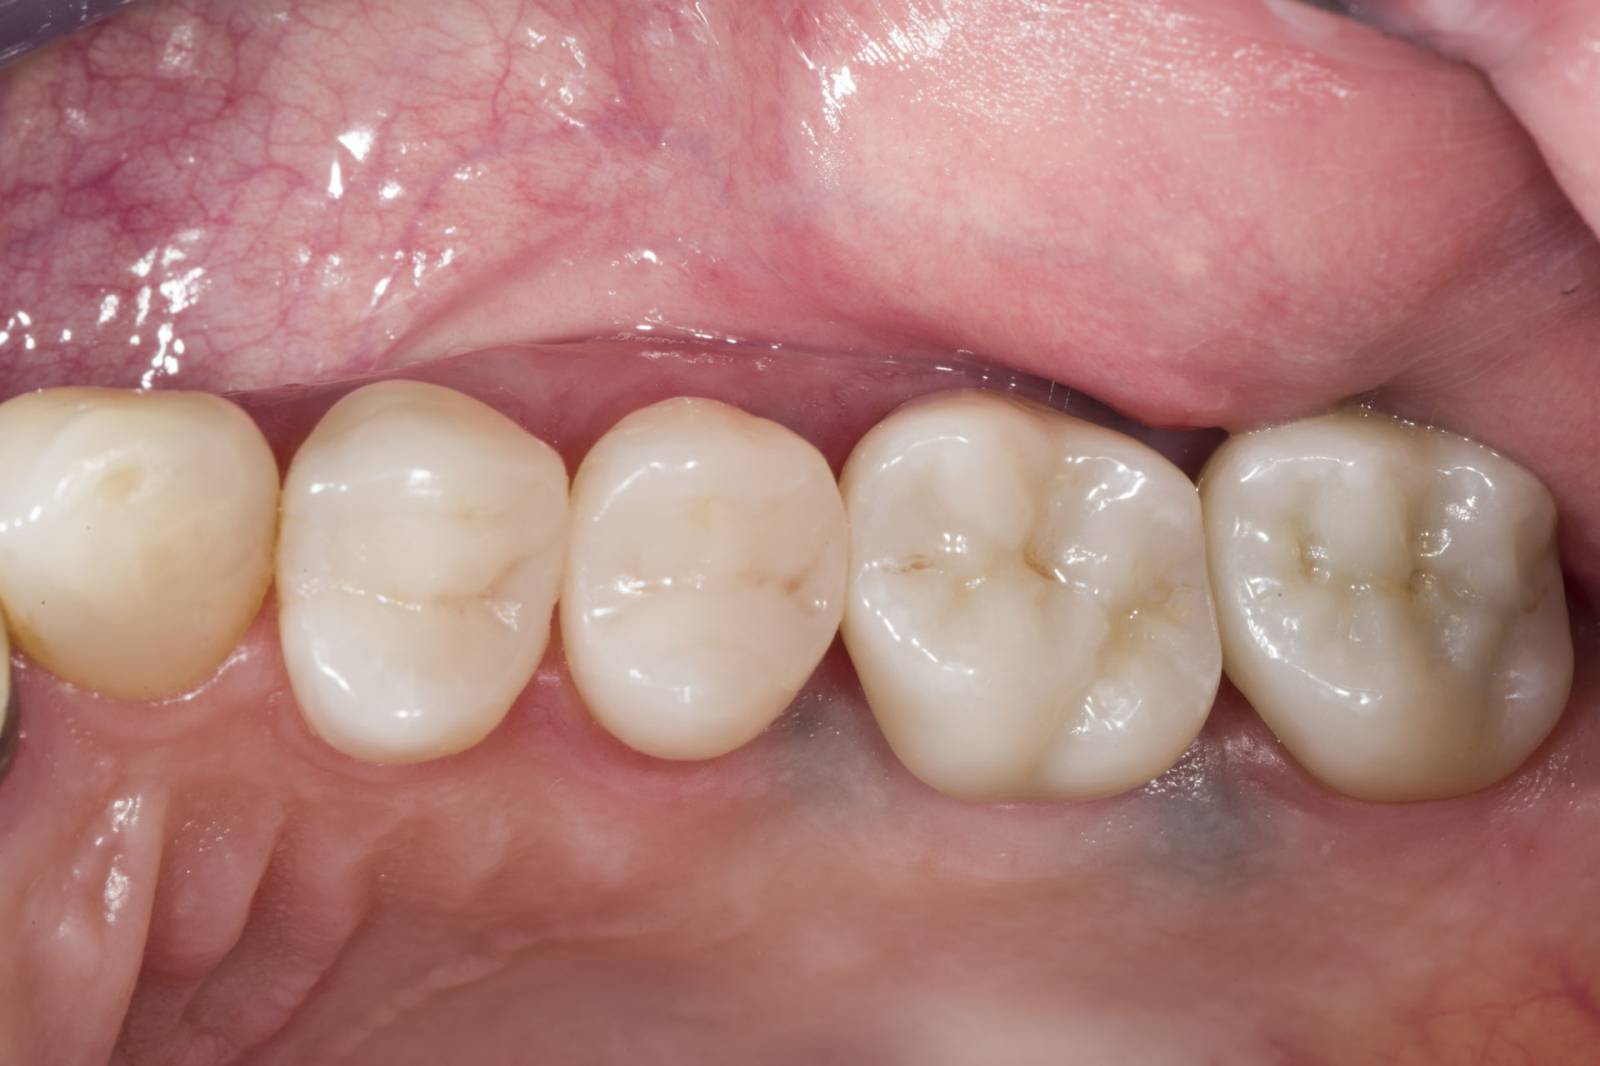

Before: Insufficient fillings in the second quadrant. The restorations were about 15 years old.

After: Chairside-fabricated crowns made from CEREC Tessera (teeth 26/27). Inlays for teeth 24 and 25 made of composite blocks.